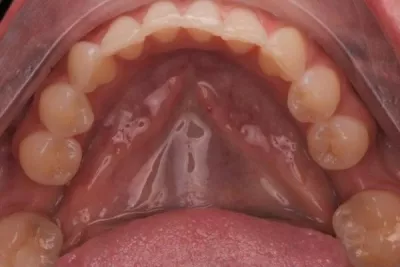

Гемисекция моляра с вертикальным переломом корня (четыре года наблюдения)

Вертикальный перелом корня (VRF) — это продольно ориентированный перелом корня, который, в зависимости от его причины, обычно начинается от апикальной части корня и распространяется на коронковую часть или наоборот, обычно обрекая зуб на удаление. Чаще встречается при эндодонтическом лечении зубов, хотя существуют и другие предрасполагающие факторы риска, которые могут спровоцировать появление трещин, приводящих к таким переломам в жизненно важных или некротизированных зубах. VRF может развиваться медленно и без каких-либо явных признаков или симптомов, что затрудняет его диагностику. Общими признаками и симптомами являются болезненность при перкуссии, легкая или тупая боль при жевании, припухлость десен, глубокий, узкий и изолированный пародонтальный карман, который обычно ассоциируется с абсцессом, и развитие J-образной рентгенопрозрачности.